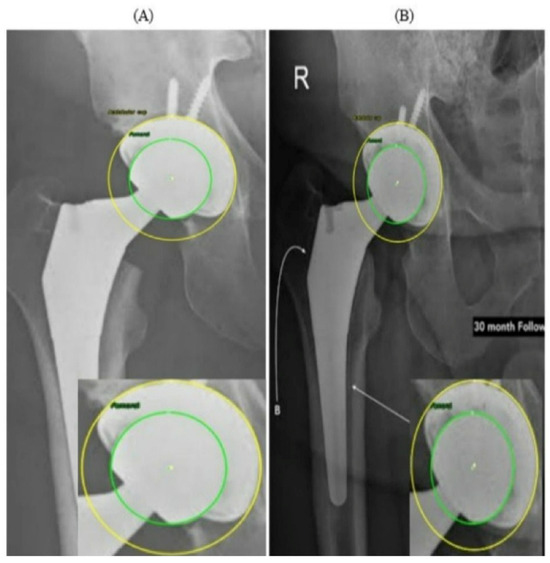

A Hybrid Automatic Model for Circle Detection in X-Ray Imagery: A Case Study on Hip Prosthesis Wear

This study presents a fully automatic hybrid framework for circle detection and geometric feature extraction from anteroposterior (AP) X-ray images. Detecting circular structures in X-ray imagery is challenging due to low contrast, noise, and metal-induced artifacts, which often limit the robustness of purely learning-based or purely geometric approaches. To address these challenges, a hybrid deep learning and computer vision pipeline is proposed that combines data-driven region localization with robust geometric fitting. A YOLOv5-based detector is first employed to identify a compact region of interest (ROI) containing circular components. Within this ROI, edge-based processing using Canny detection is applied, followed by an Edge-Snap refinement stage and robust RANSAC-based circle fitting with a Hough-transform fallback to ensure anatomically plausible circle estimation. The resulting circle centers and radii provide stable geometric parameters that can be consistently extracted across images with varying contrast, noise levels, and prosthesis appearances. The applicability of the proposed framework is demonstrated through a case study on hip prosthesis wear analysis, where the automatically detected circle parameters are used to compute medial, superior, and resultant displacement components using established two-dimensional radiographic formulations. Experimental evaluation on AP hip radiographs shows that the YOLOv5 detector achieves high ROI localization performance (mAP@0.5 = 0.971) and that the hybrid pipeline produces consistent circle parameters across longitudinal image sequences. Overall, the proposed method provides an end-to-end automatic solution for robust circle detection in X-ray imagery, with hip prosthesis wear presented solely as a case study without clinical or diagnostic claims. Full article